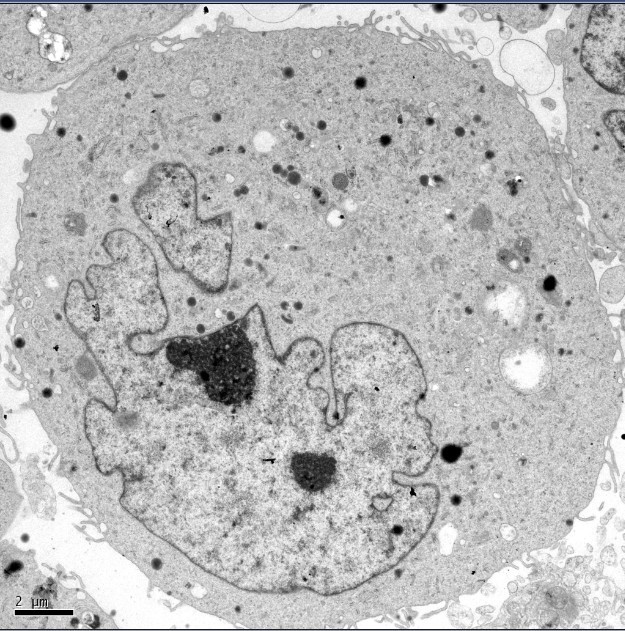

快来看快来瞧 我的细胞电镜照片~~

上传处理前和处理后的细胞照片,虫友们帮我看看处理后细胞成这样,都可能是什么原因啊?

处理后:

(就是附件里面的未命名1)

处理后理论上不能有太大变化,这结果是不是因为没固定好?细胞凋亡?还是什么可能性?

请电镜图片分析高手指点。